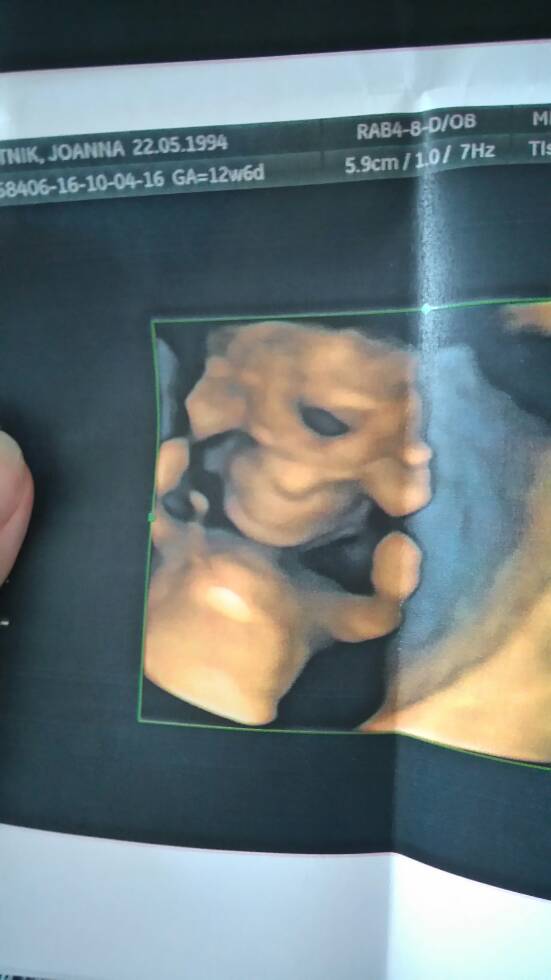

A ja nic nie widzę